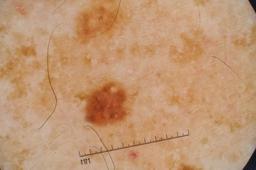

Evaluation set from the ML challenge: SIIM-ISIC Melanoma Classification.